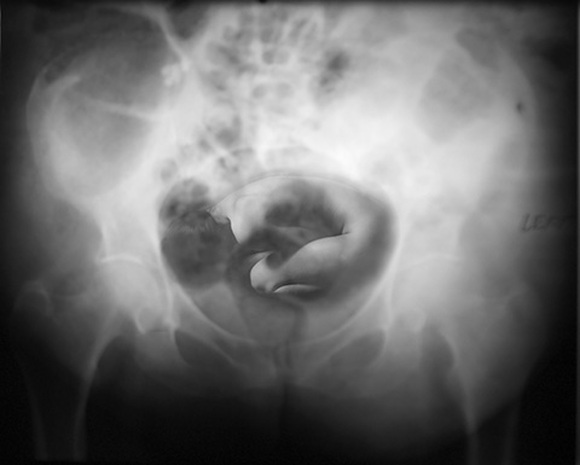

Ken Weissblum

USA

Nominee

"the Beginning"

These images are part of a series called Roentgen's Dreams which blend two apparently contradictory, yet traditional imaging techniques used with the human body: reflective photography and penetrative